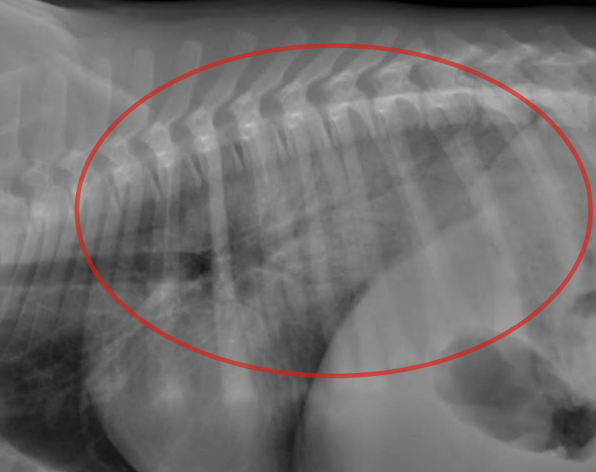

What are radiographic features of underexpansion/atelectasis?

Interstitial or alveolar lung pattern with decreased lung volume *Can be one lobe, one region, or entirely of lungs*

43

Lung Pattern?

Atelectasis *Red = alveolar pattern*

44

Atelectasis *Caudodorsal interstitial pattern*

45

Atelectasis *Moderate caudodorsal interstitial pattern*